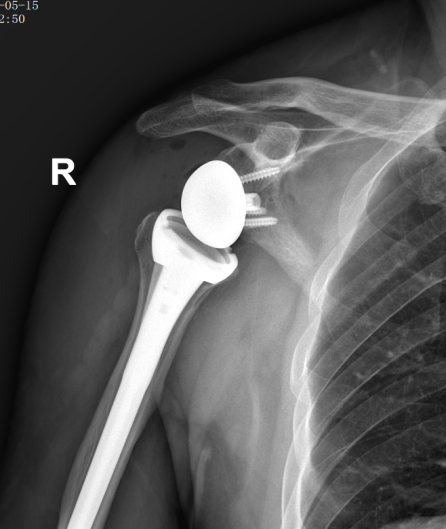

术后X线:人工关节位置良好